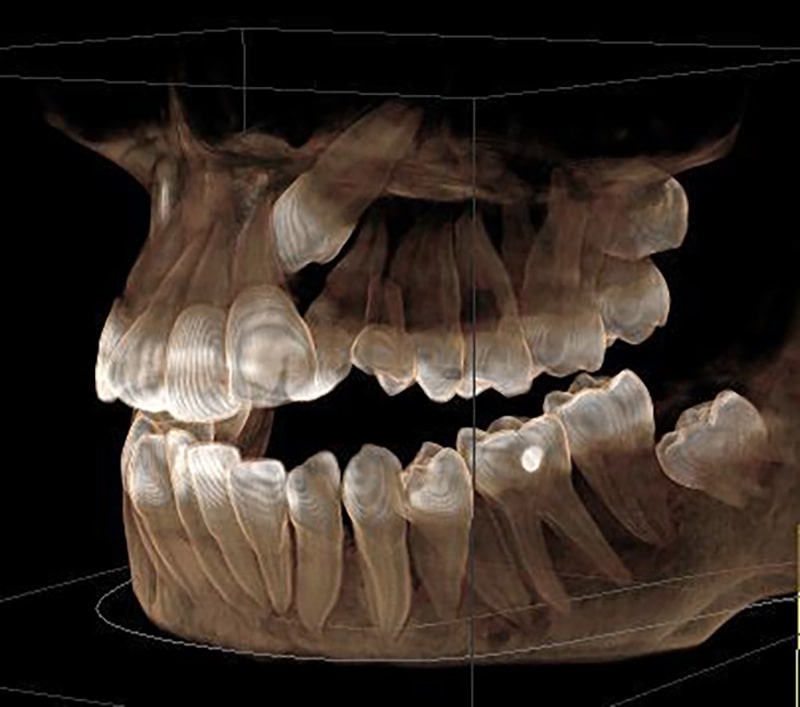

- Extraoral: Panoramic or full-jaw shots as needed

- Locating hidden (impacted) or remaining teeth

- Planning implants, root canals, or extractions